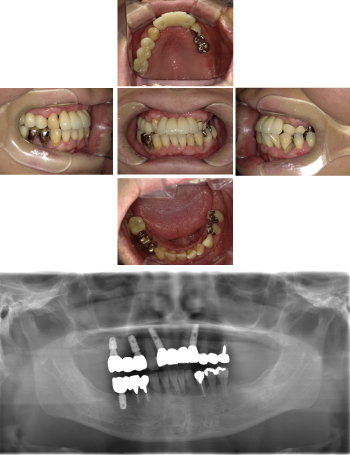

50代 インプラント治療(右上3左上3のみGBR)

| 主訴 | 入れ歯が合わず毎日ヨーグルトしか食べることができないので、しっかり咬めるインプラントにしたい。 |

| 部位 | 右下⑦⑥5④ 上顎③2①①2③ 左下67 |

| 治療期間 | 約9ヶ月 |

| 費用 | ¥4,273,500(税込) |